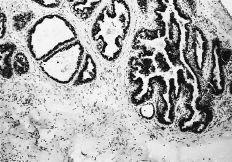

Las cuatro observaciones mostraron positividad a los RE con histocores superiores a 100. La evaluacion inmunomorfológica de los RE arrojó cifras de histocore hormonal (HH) comprendidas entre 108 y 300, con intensidades de ++/+++, en un porcentaje celular comprendido entre el 36 y el 75% (Figs. 1 y 2). La positividad a los RE se manifestaba por la presencia de inmunotinción especifica nuclear. En general, la positividad a los RE mostró un carácter de heterogeneidad de forma que no todas las áreas tumorales presentaban el mismo nivel de positividad o bien existían diferentes porcentajes en el número de núcleos marcados. En dos casos existían en periferia a las áreas tumorales imágenes de ginecomastia proliferativa, que asimismo mostraba positividad al receptor estrogénico (Fig. 3). En un caso (HH de 108) asimismo se cuantificaron en 230 fmol/mg ADN los REn mediante el método bioquímico DCC.

Fig. 1. Visión panorámica de un carcinoma ductal infiltrante con inmunorreactividad a los REn. (ERICA, 200*.)